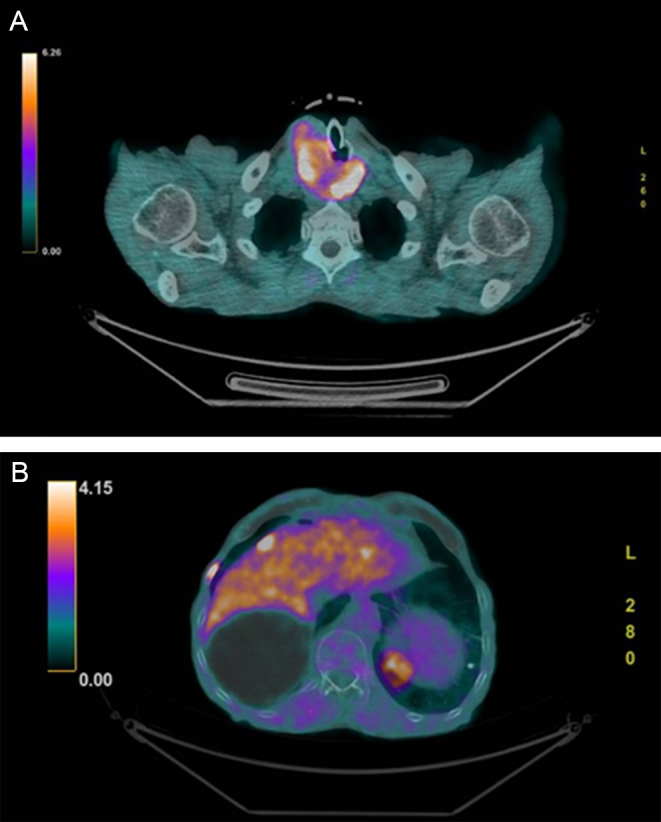

Summary: We report the case of an 88-year-old man hospitalized for COVID-19 with persistently very high procalcitonin (proCt) levels despite infection resolution. Since proCt is an adjunct tumor marker in the diagnosis of medullary thyroid carcinoma (MTC), serum calcitonin (Ct) was also measured showing very high levels. Computed tomography (CT) scan showed the presence of a thyroid mass and neck ultrasound revealed a solid isoechoic, inhomogeneous, 50 mm nodule in the right thyroid lobe, extended into the mediastinum. Fine needle aspiration (FNA) of the thyroid nodule confirmed the diagnosis of MTC. An 18F-fluorodopa positron emission tomography/computed tomography (PET/CT) scan revealed the presence of distant metastases in ribs, vertebrae, in the right iliac wing and the liver. Since surgery was not feasible, the patient was started on cabozantinib 40 mg/dL. After 16 months the patient is still on cabozantinib at the same dose, he reports complete autonomy in daily life activities, and serum Ct is still elevated; however, the imaging evaluation does not show signs of disease progression.